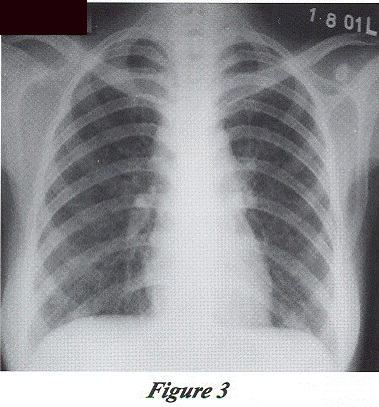

Patient attended Chest Clinic for supervised anti-TB treatment. She presented with mild cough and was afebrile. Her liver function further improved. CXR showed improving lung shadows (Figure 3).